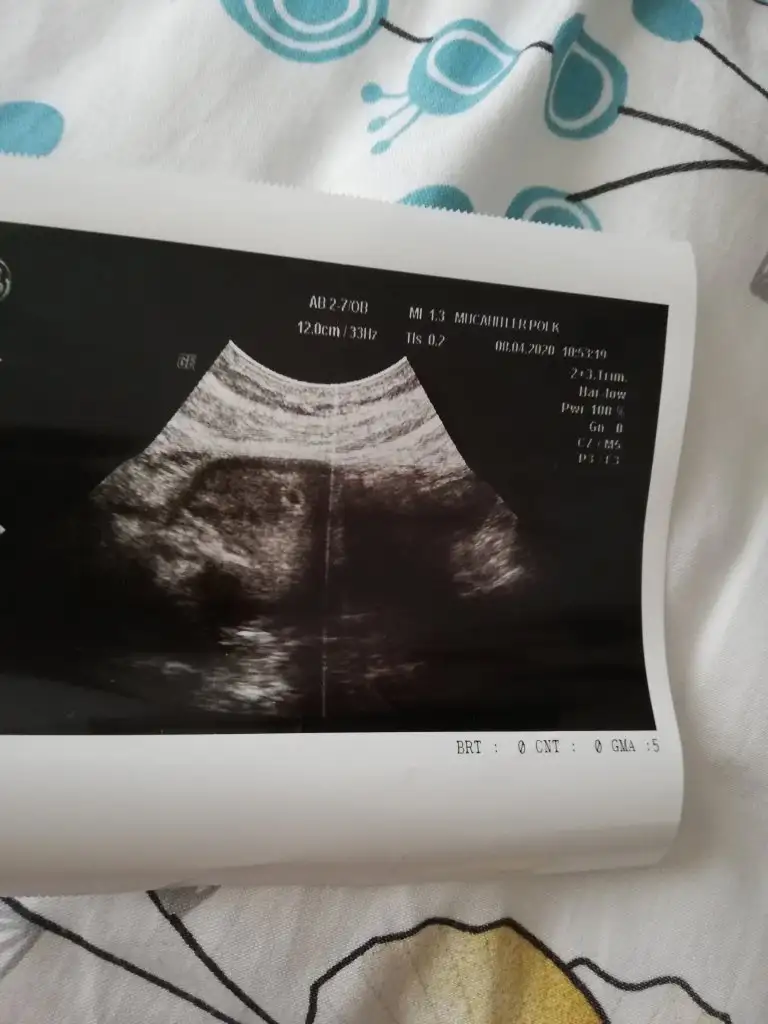

Merhaba kızlar ilk defa yazıyorum ama takip ediyorum yazdıklarınızı. Benim de adet olcak gibi karnım ağrıyor normal mi sizce. Ben yarın kese görmeye gitcem Allah izin veririse. Stres mi yapıyorum acaba ondan mı